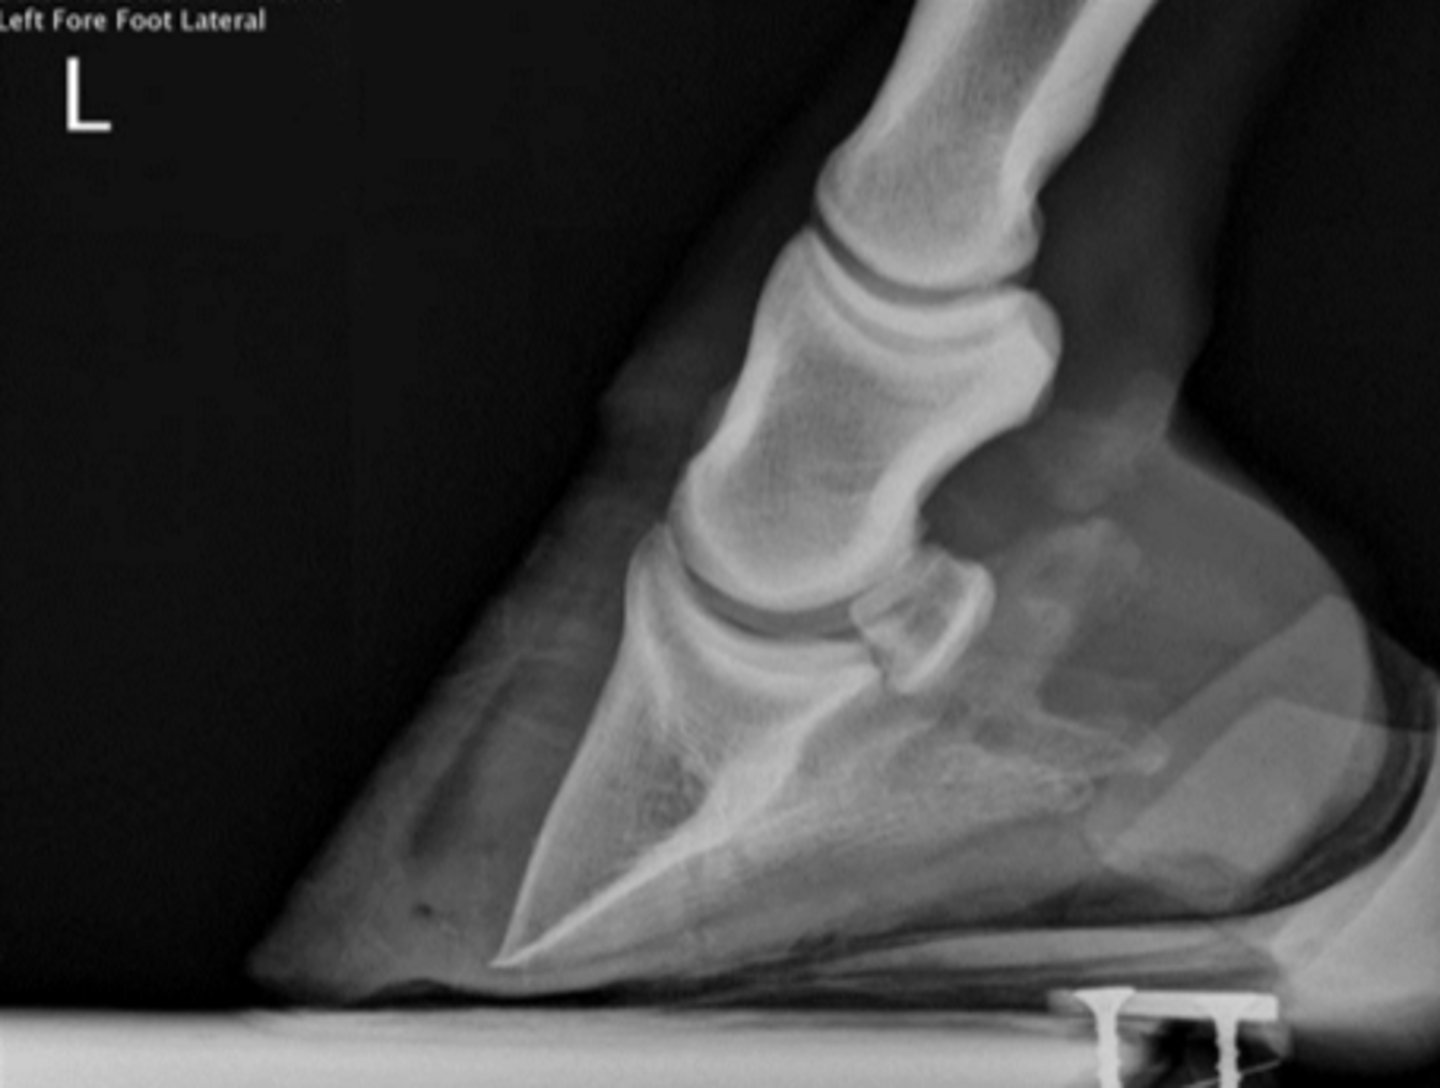

What is this radiograph depicting?

P3

What bone is fractured?

Foot cast

What type of coaptation would you apply for healing?

Suspensory ligament

What structure caused the avulsion?

Remove the middle section of the bone to remove the fracture

How is this fracture treated?